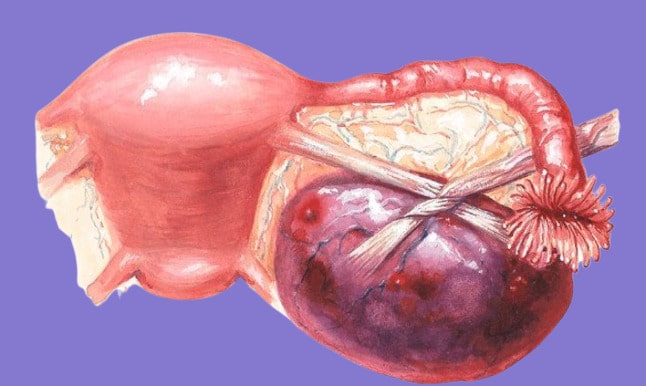

Апоплексия яичника: полное руководство по причинам, симптомам и лечению

Внезапная боль внизу живота может быть признаком апоплексии яичника. В статье подробно разбираем причины этого опасного состояния, его характерные симптомы, методы современной диагностики и все варианты…

Перекрут яичника: найти причину острой боли и сохранить здоровье женщины

Внезапная сильная боль внизу живота может быть признаком перекрута яичника, опасного состояния, требующего немедленной помощи. В статье подробно разбираем причины, симптомы, методы диагностики и современные…